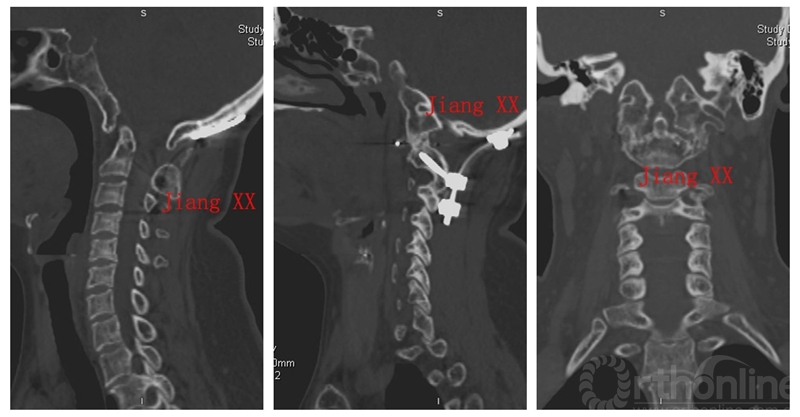

病例一:患者女性,49岁,因颈部活动受限4月入院,诊断为寰枢椎脱位,颅底凹陷。

术前CT

术后CT